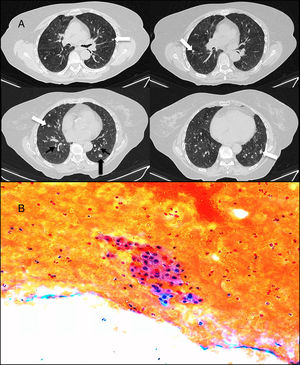

Chest X-ray and lung function tests showed no significant changes. Chest computed tomography revealed multiple solid bilateral pulmonary nodules in the left lower lobe, the largest of which measured 10mm, along with diffuse thickening of the bronchial walls and mosaic attenuation pattern suggestive of air trapping on expiration (Fig. 1A).

(A) Computed axial tomography slices in expiration, without the administration of intravenous contrast: multiple bilateral solid pulmonary nodules (white arrows), diffuse thickening of the bronchial walls (thin black arrows), associated with a mosaic attenuation pattern, suggestive of air trapping (asterisks). The nodule in the left lower lobe (thick black arrow) is the nodule that was aspirated. (B) Cytology of fine-needle aspiration-biopsy of one of the nodules, showing a group of finely granular cytoplasmic cells with slightly irregular nuclei and punctiform chromatin on a hematic background.

Fine-needle aspiration and biopsy were obtained from the largest nodule, which showed well-differentiated neuroendocrine proliferation on cytology, considered low risk due to Ki-67 negativity, suggestive of a small carcinoid tumor (Fig. 1B). This, in conjunction with radiological findings, was consistent with the diagnosis of diffuse idiopathic pulmonary neuroendocrine cell hyperplasia (DIPNECH).